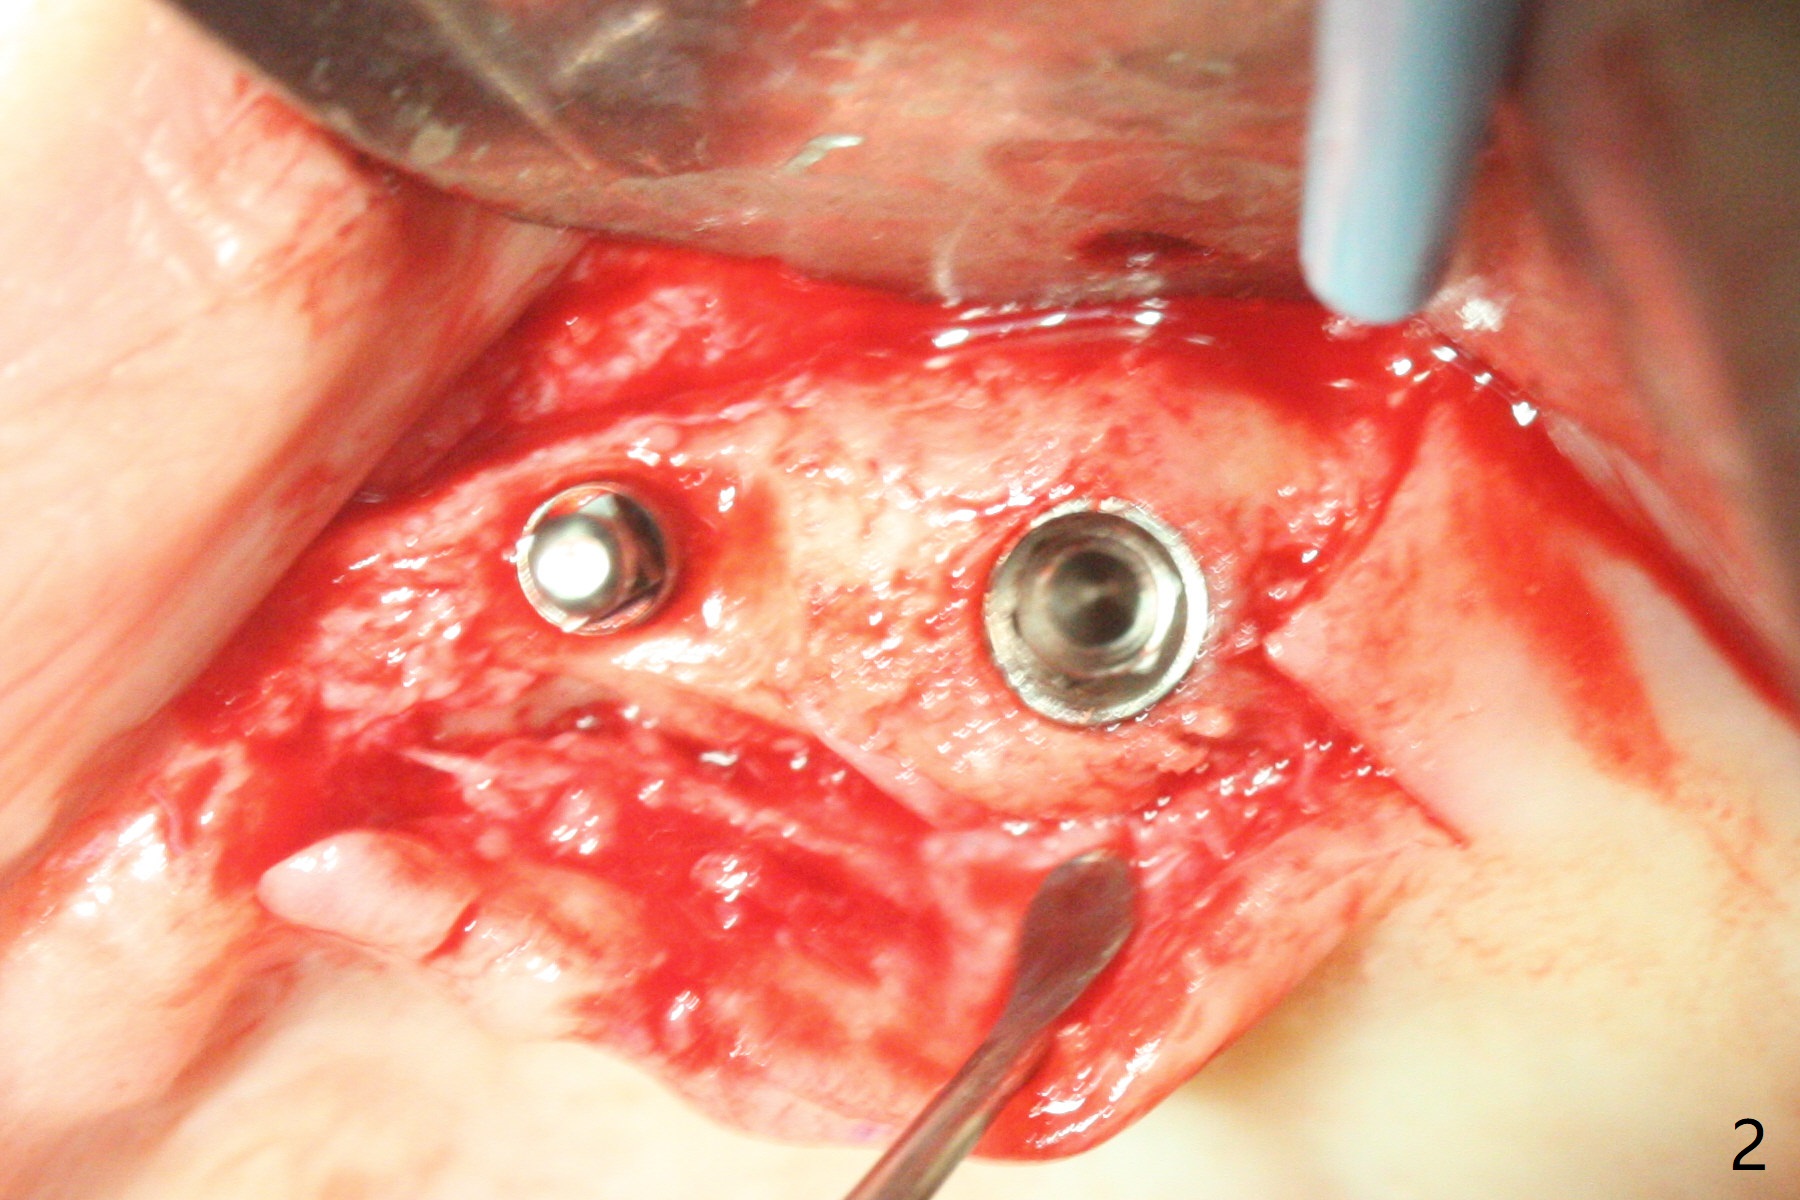

63岁女有上下活动局部假牙,由于右下侧切牙折裂(26号牙)就诊,保守处理(重新粘固)。虽然病人满意上颌义齿,而且非常害怕牙科治疗,并不想多花钱,但是对左上两个植牙固位假牙有兴趣。原计划在尖牙和第二双尖牙(11和13号牙),CT检查表明11号牙处牙槽骨太窄,所以改为12和13处种植(3.5乘10,4乘10毫米)。12号牙处牙槽嵴截除后,颊舌侧宽度仍不够,钻洞直径2毫米(图一),似乎不得不用一体式带球帽植体(1-piece implant with ball abutment),2.5乘10(4)毫米(图二至四;N: 鼻腔,S: 上颌窦),并且在它周围植骨(图三,四 *)。在假牙相对位置创造空间后,做软衬里(图五)。对于恐惧病人,尽管带球帽植体精确度要求不高,导板还是必要的。一周以后病人十分感激,因为没有痛(图六)。术后一个月她很高兴告诉我们自从植牙后,托牙下面不容易积累食物了。